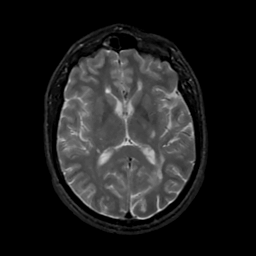

MR Study #10, April 28, 1991 -- Slice #27

[Home][Help][Clinical][Tour 1][Tour 2] Slice 27